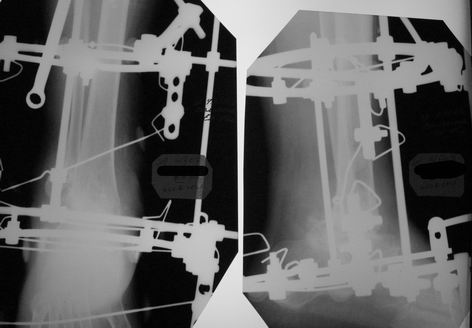

Прошу прощения за задержку с ответом. Женщину прооперировал. Из внутреннего доступа удалена внутренняя лодыжка, из наружного отсечена от рубцов латеральная, из обоих параллельно предыдущей остеотомии экономно произведена резекция "суставных" поверхностей ББК и тарана до "кровавой росы", удалены все рубцы, стопа выведена, провизорная диафиксация  спицами. Далее аппарат, однако, после удаления диафиксирующих спиц и компрессии, произошло наружное смещение тарана. Но и так время операции составило почти 4 часа, поэтому через неделю пришлось маленько подработать аппаратом. Итог на снимках (извиняюсь за качество). Не совсем все нравиться - в литературе намного красивее. Только один вопрос к уважаемому форуму: что действительно необходимо подправить?

Имя     : Вид спереди.JPG

Имя     : Вид сбоку.JPG

Имя     : Rg-граммы.jpg